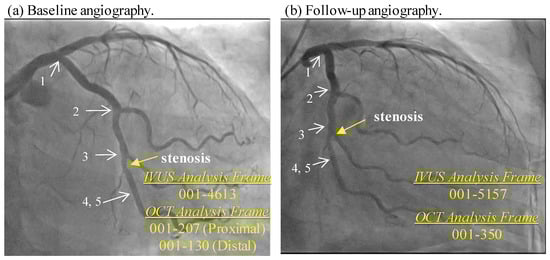

- Guo, X.; Giddens, D.P.; Molony, D.; Yang, C.; Samady, H.; Zheng, J.; Matsumura, M.; Mintz, G.S.; Maehara, A.; Wang, L.; et al. A Multi-Modality Image-Based FSI Modeling Approach for Prediction of Coronary Plaque Progression Using IVUS and OCT Data with Follow-Up. J. Biomech. Eng. 2019, 141, 0910031–0910039. [Google Scholar] [CrossRef]

- Lv, R.; Maehara, A.; Matsumura, M.; Wang, L.; Zhang, C.; Huang, M.; Guo, X.; Samady, H.; Giddens, D.P.; Zheng, J.; et al. Using Optical Coherence Tomography and Intravascular Ultrasound Imaging to Quantify Coronary Plaque Cap Stress/Strain and Progression: A Follow-Up Study Using 3D Thin-Layer Models. Front. Bioeng. Biotechnol. 2021, 9, 713525. [Google Scholar] [CrossRef]